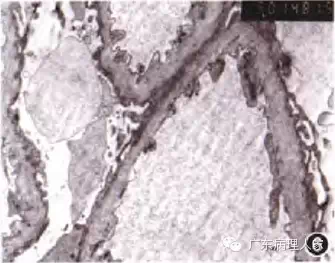

肾活检病理检查方法与一般病理学相比,也有其特殊性:肾穿刺标本体积较小,肾脏的结缔组织较少,光镜标本应该用4%中性甲醛或冰乙酸和乙醇(FAA)混合固定液,以免组织变脆,并为进行免疫病理学检查时多保留抗原;免疫荧光标本应以生理盐水低温条件下保持湿度;电镜标本应以3%戊二醛短期固定。肾活检病理检查需要免疫病理学、光学显微镜(光镜)和电子显微镜(电镜)的综合检查,各有不可替代的作用,缺一不可。(1)免疫病理学检查:很多肾脏疾病由于变态反应引起,与非变态反应肾疾病的治疗方法截然不同,所以肾活检病理检查必须进行免疫病理学检查,常用的方法是应用信誉好的试剂公司的荧光标记的抗体和补体,通过直接或间接免疫荧光法,观察肾组织内有无相应的抗原和补体,并作出半定量诊断,根据荧光显微镜下的荧光强度,分为(-)至(++++),这一点很重要,如+和+++的IgA的意义是不同的(图4)。免疫组织化学方法用于肾恬检病理诊断有一定缺陷,首先,肾小管上皮细胞具有大量线粒体,可产生较多的内源性生物素和内源性过氧化物酶,尽管可通过过氧化氢消除内源性过氧化物酶,但由于内源性生物素的干扰,仍有背景颜色过深的弊端,干扰对于阳性结果的判断。此外,由于肾活检病理需要阳性的定量结果,而免疫组织化学的人为干扰因素较多,不利于定量诊断,所以,肾活检病理的免疫球蛋白和补体的检查以荧光法较受推崇。不过,免疫组织化学法在观察肾活检标本时,在显示特殊细胞和特殊蛋白方面仍有不可替代的作用,如肿瘤细胞的浸润、轻链蛋白的产生部位等。(2)光镜检查:肾活检病理诊断很重视肾内细胞的增生程度、分布状态、细胞种类。与普通诊断病理学相比,肾活检病理检查的标本切片不能太厚,超过3μm的切片可造成细胞重叠,易使增生不明显的肾小球误诊为增生严重的病变。在染色方法和种类方面,不但要行HE染色,还要常规进行过碘酸雪夫(PAS)染色,过碘酸六胺银(PASM)染色和Masson三色染色,以便细致地观察肾小球毛细血管基底膜病变及根据细胞的位置辨认细胞的种类,并根据显色的特点判断特殊蛋白的沉积。各种特殊染色也很必要,如怀疑淀粉样变性肾病必须行刚果红淀粉样蛋白染色,怀疑脂蛋白沉积,应进行苏丹Ⅲ或油红0染色(图5),出现苏木精阳性的沉积物,应作铁、钙特殊染色等。(3)电镜检查:肾活检病理检查中常用透射电镜检查,有时根据需要也可进行扫描电镜和免疫电镜检查。电镜检查用于肾活检病理诊断根据需要可划分为三个层次:①必不可少的、决定性或修正性诊断作用,即不作电镜检查无法诊断或不能正确诊断的肾脏疾病。如一些遗传性肾脏疾病,免疫病理学检查阴性,光镜检查病变不明显,只有电镜检查方可作出诊断,包括薄基底膜肾小球病、Alport综合征(图6)、Fabry病、指甲-髌骨综合征、Ⅲ型胶原肾病、纤连蛋白肾病、脂蛋白肾病等。一些代谢异常、特殊沉积物肾病或早期免疫复合物介导的肾病,光凭免疫病理学和光镜检查很难做出正确诊断,包括早期淀粉样变性肾病、早期糖尿病肾病、冷球蛋白血症肾病、轻链蛋白沉积肾病,纤维样肾小球病、免疫触须样肾小球病等。②具有重要的辅助或参考价值的诊断作用,即凭免疫病理学和光镜检查只能做出初步笼统的诊断,应有电镜诊断验证,包括膜性肾病的分期、膜增生肾小球肾炎的分型,不典型膜性肾病的确诊、新月体性肾小球肾炎的分型、硬化性肾小球肾炎的病因分析等。③与免疫病理学和光镜检查的结果相互印证,保证诊断的正确性。如仅有肾小球上皮细胞足突弥漫融合而无电子致密物沉积,可证实为微小病变性肾小球病或局灶节段性肾小球硬化症;肾小球系膜区大块高密度电子致密物沉积,可证实IgA肾病;肾小球上皮细胞下驼峰状电子致密物沉积,可证实链球菌感染后急性肾小球肾炎;肾小球上皮细胞下电子致密物沉积可证实膜性肾病等。总之,电镜检查是保证正确的肾活检病理诊断的一个必要手段。

图6 Alport练合征,肾小球基底膜呈弥漫撕裂状态 ×5000